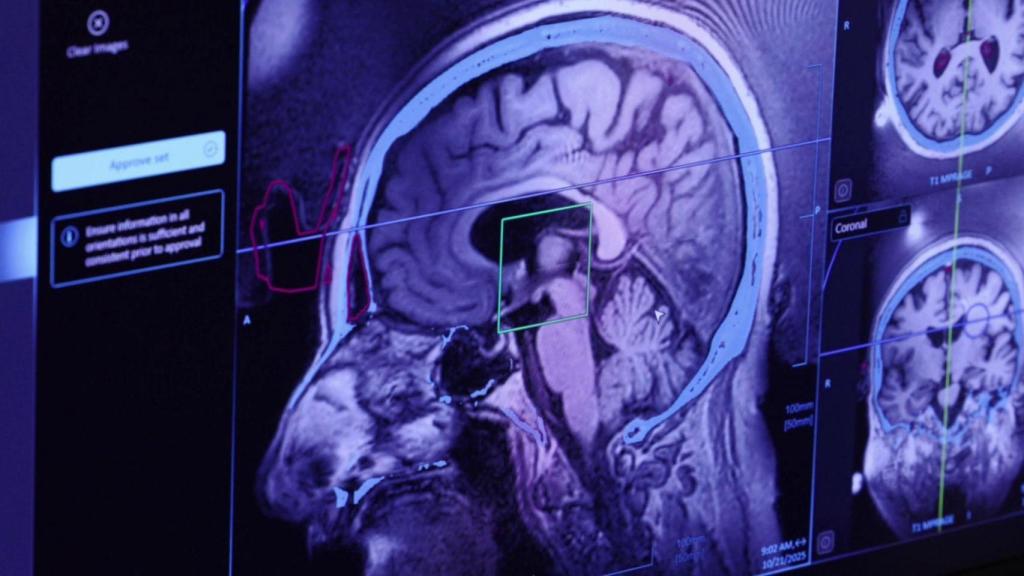

Detección de la zona del cerebro dañada a través de la tecnología HIFU, que se utiliza en el Hospital Sant Pau

En un comunicat, l'entitat sanitària trasllada aquest dijous que es tracta d'unes instal·lacions d'alta intensitat amb tecnologia MRgFUS (Magnetic Resonance Guided Focused Ultrasound) o HIFU. A més, està integrat en una resonància magnètica de Philips.

El tractament amb MRgFUS localitza mitjançant la resonància magnètica el punt exacte del cervell on s'actuarà. Posteriorment, s'apliquen els ultrasons d'alta intensitat a través del crani fins a generar una petita lesió mil·limètrica que corrigeix la deficiència que provoca el tremolor.

L'equip té una energia de 1.024 feixos d'ultrasons que convergeixen a la zona del cervell que genera el tremolor fent una petita lesió controlada (ablació tèrmica o per hipertermia). Com si fos una lupa que està travessada pel sol, exemplifiquen els experts.